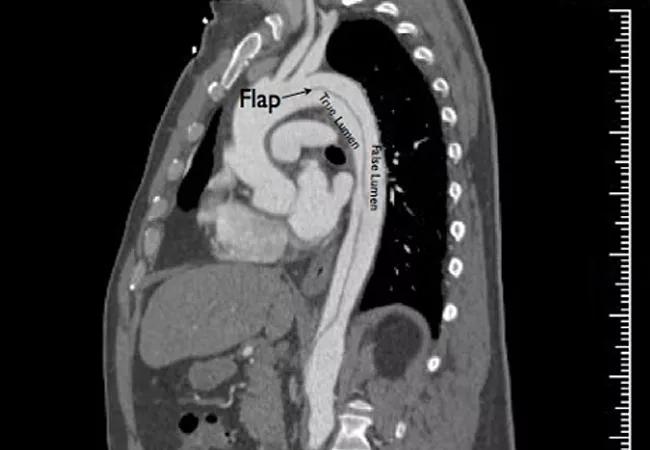

Despite significant differences in risk factors, demographics and socioeconomic factors between Black and white patients presenting with acute type B aortic dissection (TBAD), equivalent management and short-term outcomes between the two cohorts can be achieved. So finds a retrospective single-center study from Cleveland Clinic published online ahead of print in the Journal of Vascular Surgery.

TBAD anatomic features and management were statistically comparable between the two cohorts, including the proportion of patients with complicated dissection, the proportion with high-risk features in the setting of uncomplicated dissection, the proportion who underwent surgical intervention during hospitalization (40.4% for Black patients vs. 46.3% for white patients; P = 0.45) and the type of surgical intervention used.